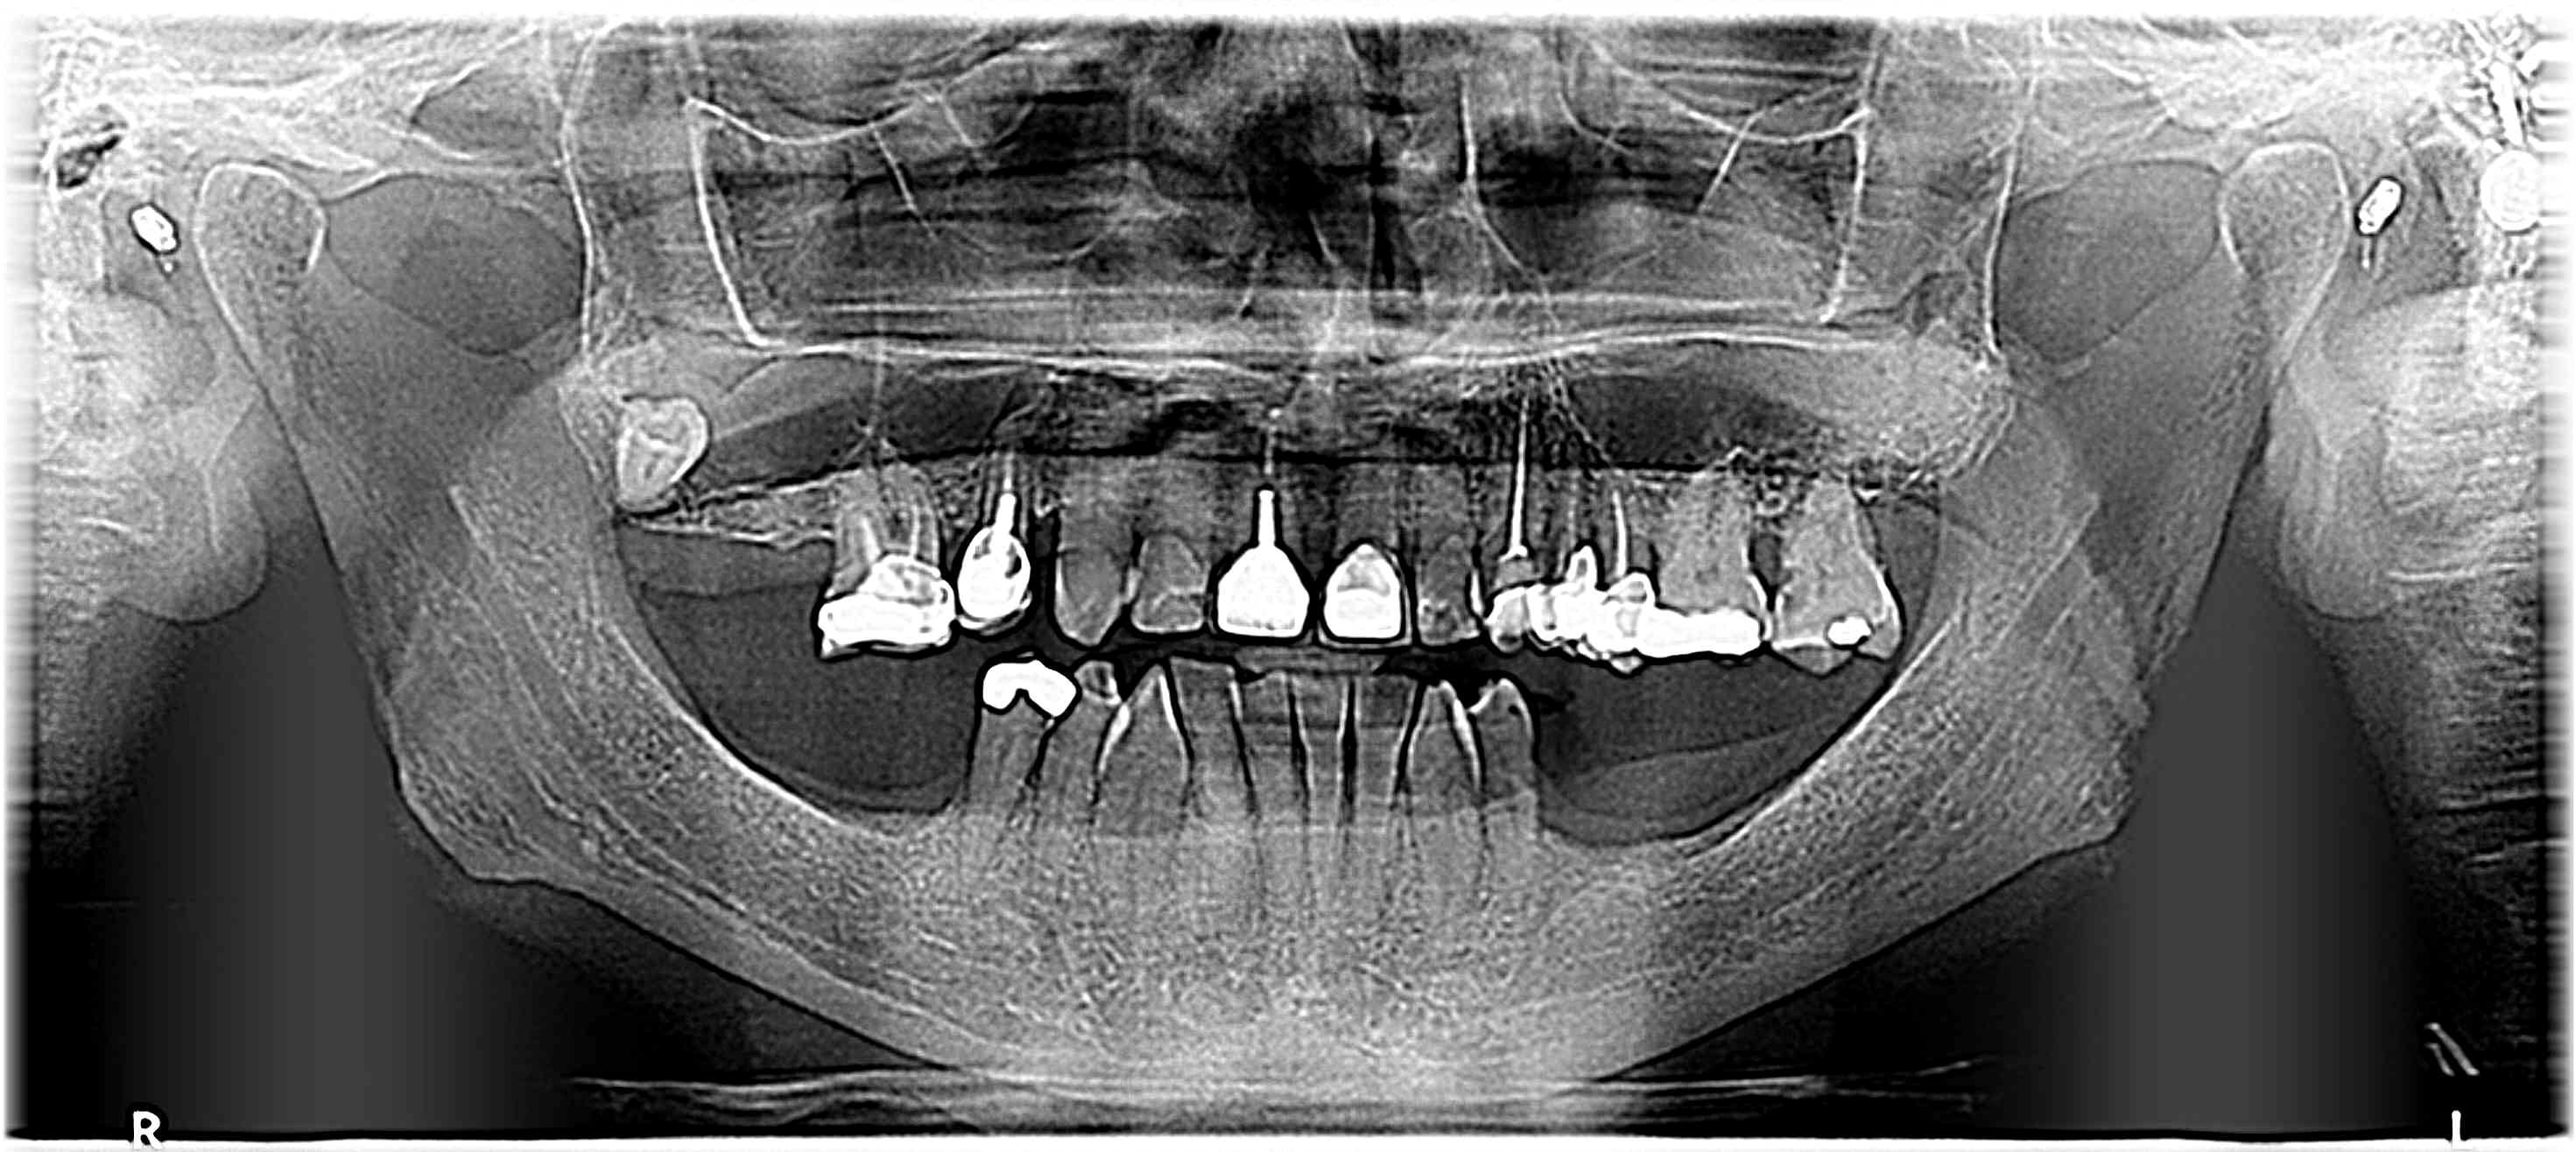

Radiologiquement je ne vois pas vraiment de rapport entre 27 et le sinus mais c'est de la 2D.

14/02/2023 à 13h18

INR=2,9.